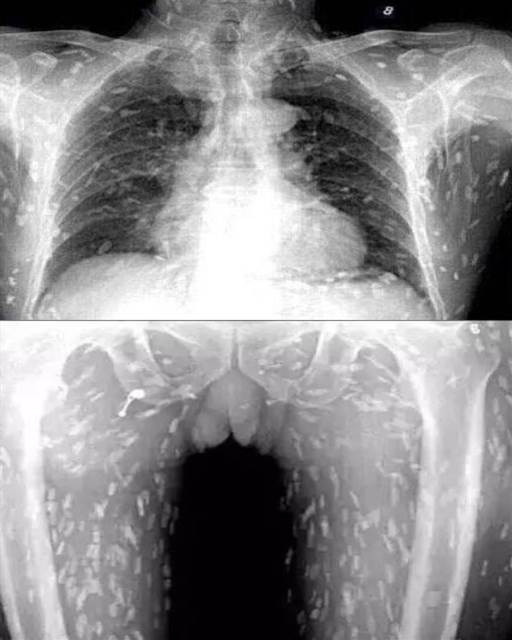

這是一個真實案例。這些X光片,來自一位經常吃生魚片的順德人。你知道身體里那些小白點是什麼嗎?是寄生蟲

。成群結隊的寄生蟲,讓身體變成一個「蟲窩」。

南方醫科大學醫生陳超介紹,淡水生魚片雖爽滑可口,但很多都有寄生蟲。它們進入人體后,會繼續繁殖生長,在體內游走。在不同的臟腑寄生,會引發不同的癥狀,嚴重時可導致死亡。